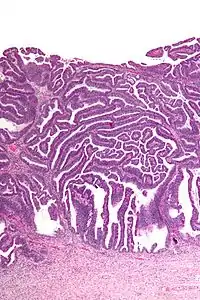

The name of the lesion describes it microscopic appearance. It has nipple-like structures with fibrovascular cores (papillae) that are long in relation to their width (villus-like), which are covered with a glandular pseudostratified columnar epithelium.

Intermediate magnification